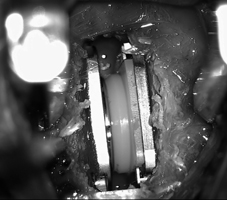

* 頸椎間盤切除合併人工椎間盤置入手術:治療效果與前述手術相當,優點是可維持頸椎關節的活動性,以避免增加鄰近節段之椎間盤活動負擔。

頸椎間盤切除合併人工椎間盤置入手術